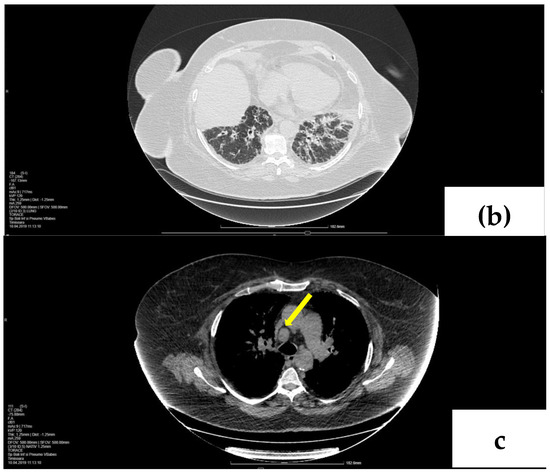

2. Case Presentation

2.1. Laboratory, Radiological, and Histological Examinations

2.2. Treatment and Outcome